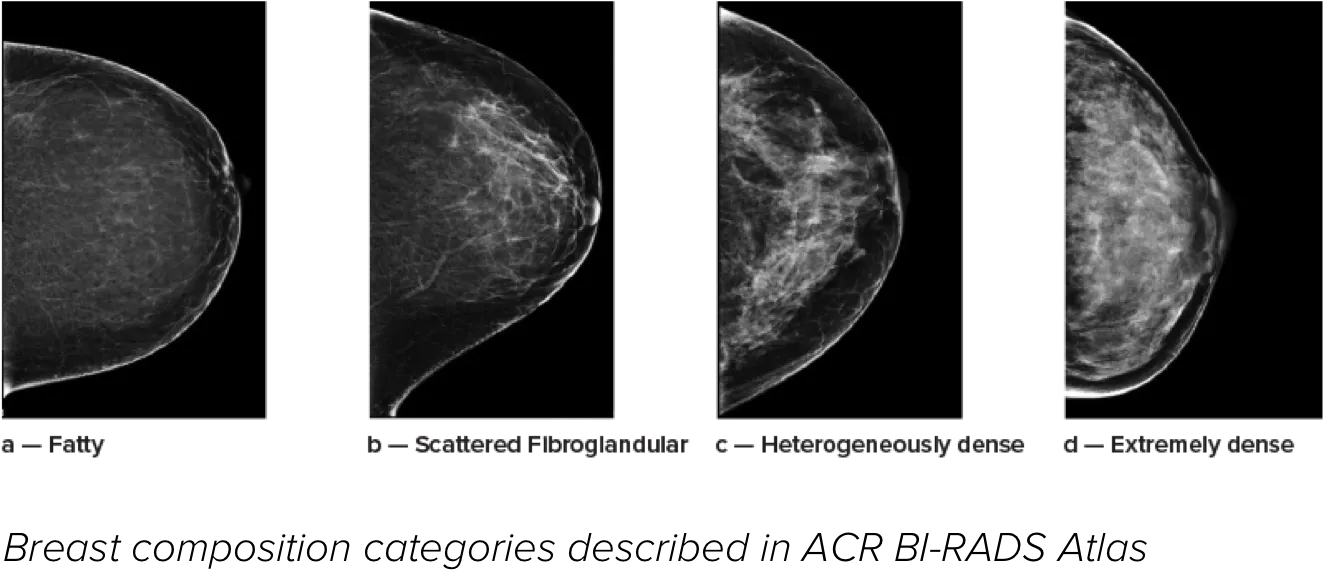

Eine höhere Brustdichte geht bekanntlich mit einem höheren Brustkrebsrisiko einher.1 Eine präzise, objektive Analyse ist daher entscheidend. Die durch maschinelles Lernen unterstützte Software der Quantra Technologie analysiert sowohl 2D™- als auch Tomosynthese-Bilder in Bezug auf Verteilung und Textur des Parenchymgewebes. Sie teilt die Brüste entsprechend der Leitlinie der 5. Auflage des BI-RADS Atlas des American College of Radiology (ACR) nach ihrer Zusammensetzung in vier Brustdichte-Kategorien ein.2

*Die Scores basieren auf den ACR BI-RADS-Kategorien nach den revidierten Leitlinien der 5. Auflage des vom American College of Radiology (ACR) herausgegebenen BI-RADS-Atlas. Dadurch werden Struktur und Textur im Vergleich zum Volumen bei der Dichtebestimmung berücksichtigt.

8. Brustzusammensetzungskategorien gemäß ACR BI-RADS-Atlas.